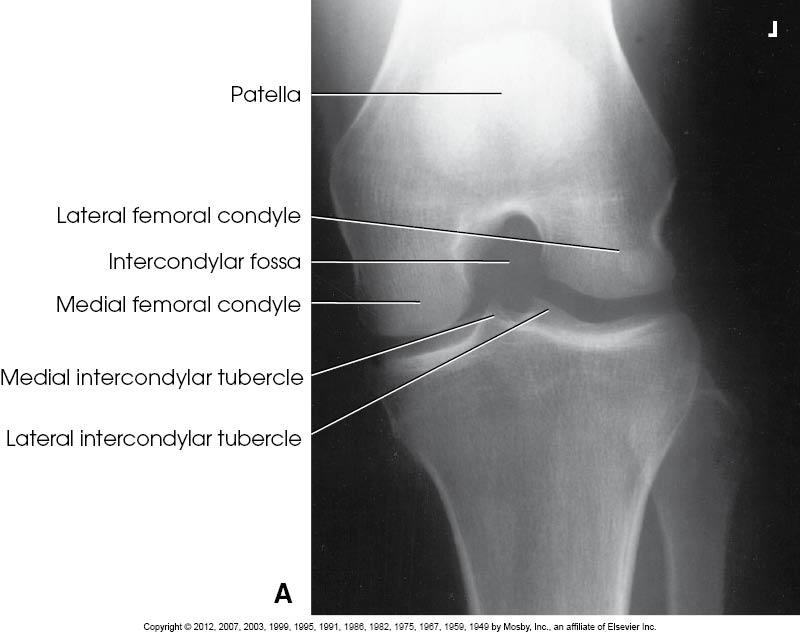

Structures Shown

• Open

intercondyloid fossa

• Intercondyloid emminences

• Knee

joint

• Soft tissue

PA axial of the intercondyloid fossa, Holmbland Method